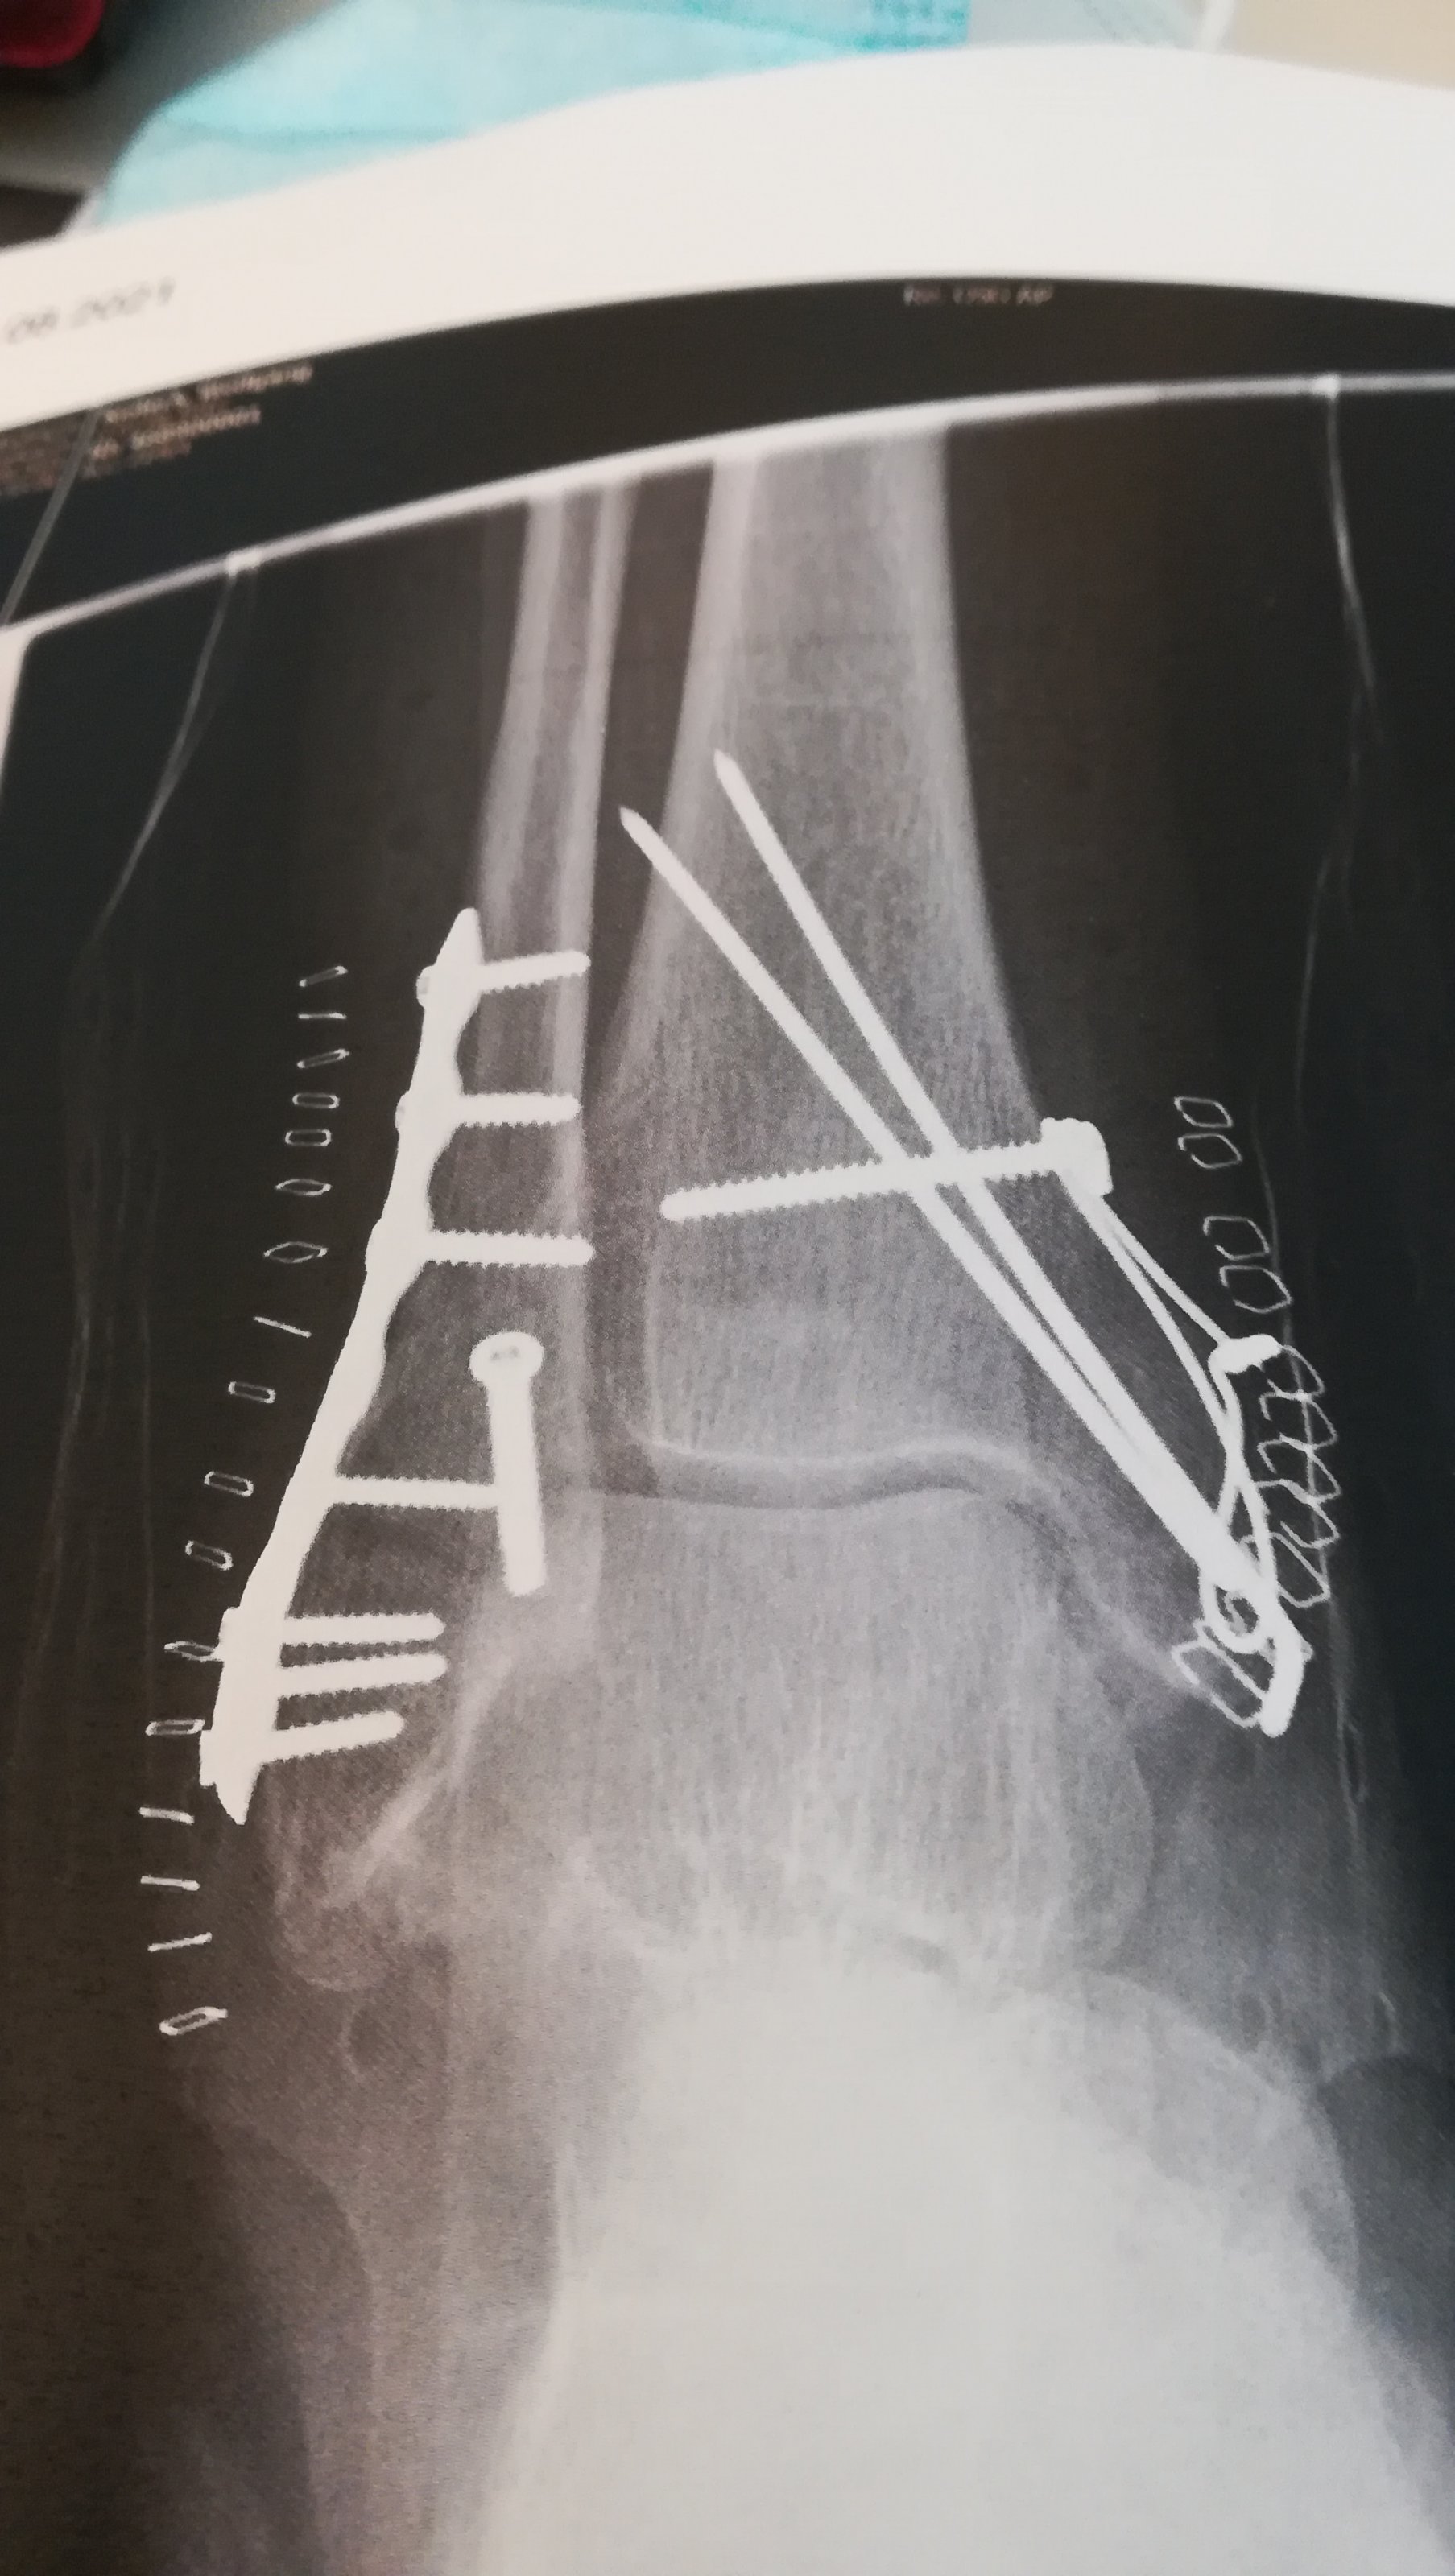

Sieht aus wie in ner Schraubenkiste ;-)...GUTE BESSERUNG!!Kurzes Update, Mein Fuß nach der Instandsetzung.Anhang anzeigen 430687Anhang anzeigen 430688

Danke, und das beste ist ich darf den ganzen Kram behalten.Sieht aus wie in ner Schraubenkiste ;-)...GUTE BESSERUNG!!

Schätze das Zeug wert, Titan ist teuerDanke, und das beste ist ich darf den ganzen Kram behalten.